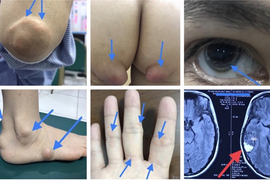

Một gia đình tại miền Bắc có tới 28 người cùng mang đột biến gen di truyền gây xơ vữa mạch, đột quỵ, có thể thiệt mạng trước tuổi 20.